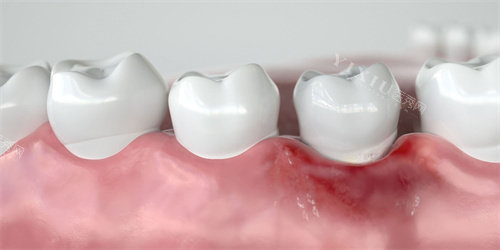

近段日子,我饱受牙龈萎缩的困扰。一开始,只是刷牙时偶尔出血,我没太在意,觉得可能是上火或者刷牙太用力了。可后来,牙龈越来越红肿,牙齿也开始隐隐作痛,甚至牙根都露出来了,不仅影响美观,还让我吃东西变得小心翼翼,生怕碰到敏感的牙根。我意识到,这可不是小问题,必须得去看医生了。

我怀着忐忑的心情走进了牙科诊所。医生让我躺在治疗椅上,仔细地检查了我的口腔。他一边检查一边给我讲解:“你的牙龈萎缩情况比较重的,主要是由于牙周病、刷牙不当等原因导致的。长期的牙菌斑堆积引发了牙周炎症,再加上你可能刷牙方式不太对,对牙龈造成了损伤,所以牙龈才会慢慢退缩。” 听到这些,我心里既自责又害怕,自责自己没有早点重视口腔健康,害怕牙齿保不住。

医生接着说:“牙龈萎缩是一种不可逆转的疾病,治疗只能减缓其进展,对于你现在的情况,要想改善,可能需要进行一些治疗。” 他给我列举了一些治疗方法,比如先治疗牙周疾病,通过洗牙、刮治等方式清除牙菌斑和牙结石,控制炎症;然后根据改善情况,再考虑是否进行牙龈填充手术。我心里很犹豫,手术听起来就很可怕,而且也不知道结果怎么样。医生似乎看出了我的顾虑,安慰我说:“现在的技术很成熟,不用太担心,我们会根据你的具体情况制定较适合你的方案。”